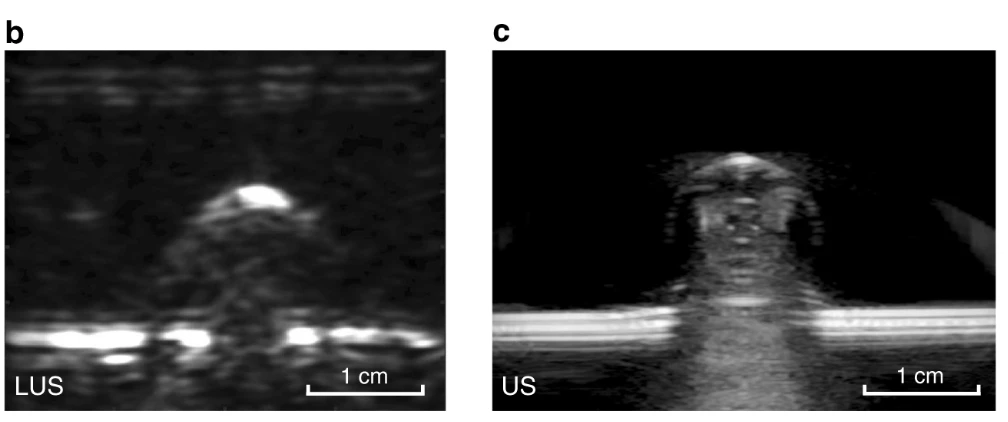

An image slice of porcine tissue. Laser ultrasound on the left, traditional ultrasound on the right

In the new study, the researchers demonstrate the successful development of this novel laser ultrasound technique, from initial tests on a gelatin mold resembling human skin, to excised animal tissue. The study ultimately demonstrates the method’s efficacy in human volunteers, presenting the first non-contact laser ultrasound images of a human forearm.

At this point the method does not deliver images at resolutions equal to conventional ultrasound techniques, however, the researchers suggest this is just the first developmental milestone to be crossed. The system can potentially be refined and improved to deliver finer tissue detail.